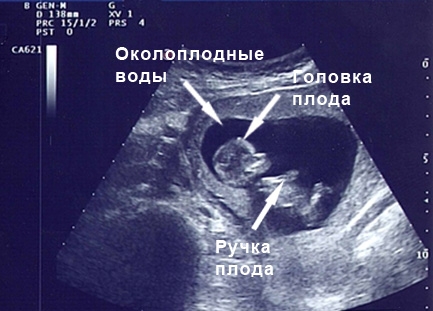

УЗИ: 25 неделя беременности

На этой неделе при ультразвуковом исследовании особое внимание уделяется околоплодным водам и их объему. Специалисты измеряют длину всех костей малыша. Позвоночник уже полностью развит. Ноздри ребенка открыты, в то время как еще неделю назад они были закрыты. Малыш активно реагирует на знакомые голоса, проявляя движения.